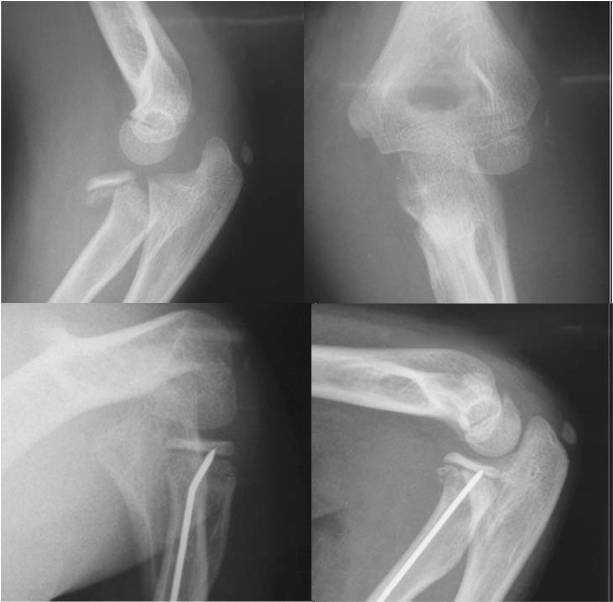

8 岁女孩桡骨颈骨折。

接近 90 度(>30度)成角的桡骨颈骨折,仍首先尝试 Patterson 与以色列法等闭合复位方法.

难推动倒斜下的桡骨颈,闭合复位失败,2.0 克氏针扁头经皮撬拨骨折断端,克氏针钝头复位骨折。

取出复克氏针,已经比较稳定,但侧片看见桡骨近端仍有轻微向后、外移位趋势,存在潜在不稳定。

1.5 克氏针固定,避免向后外移位趋势(术后正、侧位X线片及置针的肘部外观)

很显然我们按红箭头走了 Timothy 的路线图。